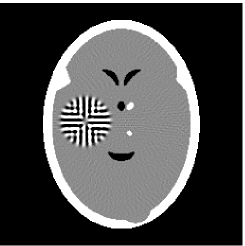

Furthermore, we used the classic ART iteration as the iteration operator in our numerical experiments. In order to compare the proposed superiorization algorithm with the classic superiorization algorithm, we applied the classic superiorization and -PP superiorization algorithm to two phantoms (see figure 1). The first one is the Shepp-Logan phantom[30], and the second one is the head phantom with a ghost which is invisible at 22 specified projection directions [10, 31]. In addition, we compare the performances of the two algorithms for the noiseless and noised data with different projections. In all experiments, the noised projection data was corrupted by additive Gaussian white noise with variance . We record the iterations, running time of program and mean square error (MSE) of different algorithms, where MSE is computed by

Noiseless projection data: Since the ghost in this phantom is invisible at 22 directions [10, 11], the reconstruction images usually suffer from artifacts. in our simulations, the projection data were collected in 112 and 82 directions: 90 and 60 with equal angle increments from to and 22 specified views in which the ghost is invisible [10]. Iteration procedures were terminated when for the noiseless projections.

The reconstruction images from the noiseless projection data were shown in the Fig. 6. For comparison, Table 3 present the iterations, MSE, Res and running time(RT) of different reconstruction results.